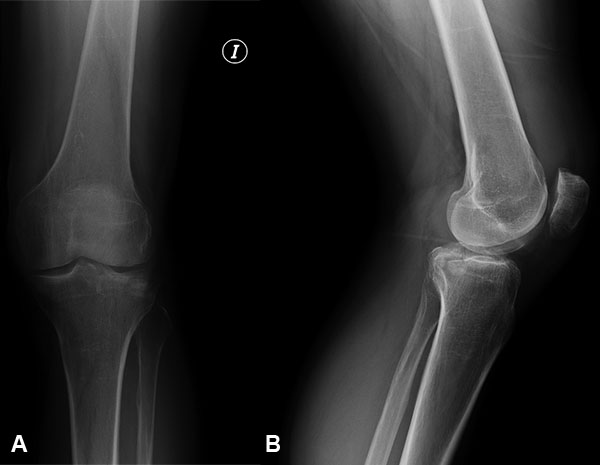

El diagnóstico se realizó siguiendo los hallazgos clínicos, radiográficos, de la tomografía computada o la RMN según el caso (figs. 1 a 7).

Figura 1: Masculino, 48 años, Schatzker 1.

Figura 2: Mismo paciente imagen TAC.